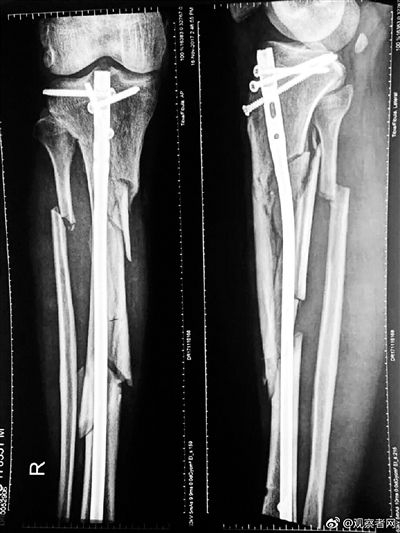

这起案件发生于2017年10月18日,安次警方通报称,当天17时许,四名歹徒持镐将廊坊城南医院院长张某打伤,致其右腿粉碎性骨折。

张毅的女儿张晶(化名)几年前从国外留学回来后在北京上班,去年下半年她刚做了母亲,“去年10月18日,父亲被人打伤了,考虑到我还在哺乳期,他当时和母亲在廊坊都没有告诉我这个消息,怕影响我的情绪。”